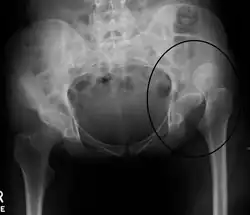

X-ray showing a joint dislocation of the left hip. | |

Typically, people with hip dislocations present with severe pain and an inability to move the affected leg.[1][4] Diagnosis is made by physical exam and plain X-rays of the hips. A CT scan is recommended following reduction to rule out complications. Complications include osteonecrosis, femoral head fractures, and posttraumatic osteoarthritis.[12][13]

An anterior-posterior (AP) X-ray of the pelvis and a cross-table lateral X-ray[24] of the effected hip are ordered for diagnosis.[4][5][16] The size of the head of the femur is then compared across both sides of the pelvis. The affected femoral head will appear larger if the dislocation is anterior, and smaller if posterior.[7] A CT scan may also be ordered to clarify the fracture pattern.[20]